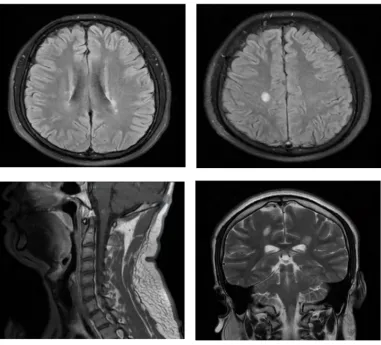

病例一 小崔是一個(gè)身強(qiáng)力壯的大四學(xué)生,即將離開校園步入社會(huì),一天早上起床感覺(jué)頭暈,伴有惡心和嘔吐,自覺(jué)四肢麻木,看東西出現(xiàn)雙影,第二天出現(xiàn)走路不穩(wěn),在家人的陪同下去了當(dāng)?shù)乜h醫(yī)院,診斷“前庭神經(jīng)炎”,輸液治療,癥狀沒(méi)有明顯好轉(zhuǎn)。小崔的母親非常著急,帶著小崔來(lái)到滄州市中心醫(yī)院神經(jīng)免疫、中樞神經(jīng)系統(tǒng)感染二科就診,劉潔瓊主任團(tuán)隊(duì)通過(guò)詳細(xì)地詢問(wèn)病史、查體,對(duì)患者進(jìn)行了腰椎穿刺顯示寡克隆區(qū)帶(+),頭頸胸部增強(qiáng)核磁共振顯示大腦和腦干多發(fā)異常信號(hào),再次追問(wèn)病史,小崔入院前4月余曾有右側(cè)肢體麻木,未予重視,自行好轉(zhuǎn),判斷小崔所患的疾病是復(fù)發(fā)緩解型多發(fā)性硬化,立即給予患者激素沖擊治療,數(shù)天后小崔癥狀完全緩解。為了防止疾病再次復(fù)發(fā)對(duì)小崔日后的生活和工作造成影響,劉潔瓊主任結(jié)合國(guó)際最新研究成果及指南,給予患者生物制劑皮下注射,患者目前無(wú)不良反應(yīng),已經(jīng)進(jìn)入工作崗位開始了新生活。 病例二 張女士?jī)赡昵吧⒆雍蟪霈F(xiàn)右眼視物模糊,就診于當(dāng)?shù)蒯t(yī)院診斷為視神經(jīng)炎,一直服用免疫抑制劑治療。半月前的一天張女士感覺(jué)背部發(fā)麻,以為著涼,未予重視,后來(lái)張女士又出現(xiàn)了雙下肢麻木無(wú)力、走路不穩(wěn),同時(shí)自覺(jué)排尿、排便費(fèi)力,張女士的家人馬上意識(shí)到了問(wèn)題的嚴(yán)重性,趕緊帶著張女士就診于滄州市中心醫(yī)院急診入住脊髓外科?;颊甙Y狀進(jìn)行性加重,起初尚能行走,短短兩天已進(jìn)展至臥床狀態(tài),下肢抬起困難,身體麻木感也發(fā)展到胸部及以下,完善脊髓核磁掃描顯示脊髓長(zhǎng)節(jié)段異常信號(hào)伴腫脹,考慮中樞神經(jīng)系統(tǒng)脫髓鞘病,遂轉(zhuǎn)往醫(yī)院神經(jīng)免疫、中樞神經(jīng)系統(tǒng)感染二科,劉潔瓊主任團(tuán)隊(duì)細(xì)致詢問(wèn)病史、查體,并進(jìn)行腰椎穿刺顯示水通道蛋白4抗體(+),判斷張女士所患疾病為視神經(jīng)脊髓炎譜系疾病,立即給予激素沖擊治療,數(shù)天后張女士的癥狀逐漸恢復(fù)正常。 視神經(jīng)脊髓炎譜系疾病是由水通道蛋白4抗體介導(dǎo)的中樞神經(jīng)系統(tǒng)脫髓鞘疾病,主要表現(xiàn)為反復(fù)發(fā)作的視神經(jīng)炎和橫貫性脊髓炎,90%以上為多時(shí)相病程,其中40-60%在1年內(nèi)復(fù)發(fā),約90%在3年內(nèi)復(fù)發(fā),任何一次臨床發(fā)作均有可能帶來(lái)不可逆性損傷,因此,視神經(jīng)脊髓炎譜系疾病一經(jīng)診斷后應(yīng)盡早開始序貫治療并堅(jiān)持長(zhǎng)程規(guī)律預(yù)防。 病例三 小魏是個(gè)14歲的初中生,一天“感冒”后出現(xiàn)發(fā)熱,體溫在37.5-37.7℃之間,口服退熱藥后堅(jiān)持上學(xué)?!案忻啊眱商旌蟮那宄浚∥撼酝暝顼垳?zhǔn)備去上學(xué),突然出現(xiàn)四肢抽搐伴意識(shí)不清,伴舌咬傷,持續(xù)數(shù)分鐘后抽搐好轉(zhuǎn),但仍意識(shí)模糊,躁動(dòng)不安,這可嚇壞了小魏的父母,趕緊帶著孩子來(lái)到了滄州市中心醫(yī)院神經(jīng)免疫、中樞神經(jīng)系統(tǒng)感染二科,劉潔瓊主任詳細(xì)查看病人后立即進(jìn)行頭顱CT、抽血化驗(yàn)和腰椎穿刺術(shù),腦脊液結(jié)果顯示MOG抗體(+),判斷小魏是MOG抗體相關(guān)性腦炎,經(jīng)過(guò)治療小魏第二日神智轉(zhuǎn)清,半月后好轉(zhuǎn)出院,重歸課堂。 神經(jīng)免疫、中樞神經(jīng)系統(tǒng)感染二科 滄州市中心醫(yī)院神經(jīng)內(nèi)科醫(yī)學(xué)中心神經(jīng)免疫、中樞神經(jīng)系統(tǒng)感染二科是國(guó)家臨床重點(diǎn)??苿?chuàng)建單位、河北省臨床重點(diǎn)建設(shè)??啤嬷菔信R床重點(diǎn)學(xué)科,是中國(guó)罕見病聯(lián)盟腦炎base數(shù)據(jù)庫(kù)成員單位,是國(guó)家區(qū)域醫(yī)療中心河北省神經(jīng)免疫疾病聯(lián)盟成員單位,致力于中樞神經(jīng)系統(tǒng)自身免疫性疾病和感染性疾病的醫(yī)療、教學(xué)、科研、預(yù)防、保健和康復(fù)工作。擁有一支經(jīng)驗(yàn)豐富、技術(shù)精湛、業(yè)務(wù)素質(zhì)過(guò)硬的專業(yè)技術(shù)隊(duì)伍,現(xiàn)有碩士生導(dǎo)師1名,主任醫(yī)師1名、副主任醫(yī)師1名、主治醫(yī)師2名,博士研究生1名,碩士研究生4名。科室立足國(guó)際視野,為神經(jīng)免疫和中樞神經(jīng)系統(tǒng)感染性疾病患者提供最先進(jìn)的診療理念。科室病房在十樓東區(qū),門診在腦科醫(yī)院二樓2診室,劉潔瓊主任每周二、四出診,黃秋海主任每周六、日出診。科室全體醫(yī)護(hù)人員將銳意進(jìn)取、奮楫篤行,用精湛醫(yī)術(shù)和人文關(guān)懷為廣大患者提供一流的服務(wù)。 科室診療范圍: 1.以臨床孤立綜合癥、多發(fā)性硬化、脊髓炎、視神經(jīng)脊髓炎譜系疾病、急性播散性腦脊髓炎、同心圓硬化、瘤樣炎性脫髓鞘病等為代表的中樞神經(jīng)系統(tǒng)炎性脫髓鞘性疾病。 2.腦橋中央髓鞘溶解癥、腦橋外髓鞘溶解癥、腦白質(zhì)營(yíng)養(yǎng)不良。 3.各種感染性腦炎、腦膜炎,包括病毒性腦炎/腦膜炎,化膿性腦膜炎、結(jié)核性腦膜炎、真菌性腦膜炎、朊蛋白病、腦囊蟲病、神經(jīng)梅毒等。 4.自身免疫性腦炎和小腦炎,包括抗NMDA受體抗體、抗LG1抗體、抗GABA受體抗體等腦炎。 5.中樞神經(jīng)系統(tǒng)血管炎 6.重癥肌無(wú)力 7.神經(jīng)系統(tǒng)副腫瘤綜合癥 8.其他中樞神經(jīng)系統(tǒng)與自身免疫相關(guān)的疾病和疑難雜癥 科室特色技術(shù)項(xiàng)目: 1、神經(jīng)免疫亞專業(yè):為神經(jīng)系統(tǒng)免疫性疾病患者提供全面?zhèn)€體化的治療方案,包括急性期激素沖擊、血漿置換、免疫吸附、丙種球蛋白治療和緩解期的免疫抑制治療,以及多發(fā)性硬化的免疫修正治療,與胸外科合作進(jìn)行重癥肌無(wú)力患者經(jīng)胸腔鏡微創(chuàng)胸腺摘除術(shù),與神經(jīng)外科合作為疑難患者開展立體定向腦活檢手術(shù)。 2、中樞神經(jīng)系統(tǒng)感染亞專業(yè):開展腦脊液細(xì)胞學(xué)、病原微生物二代測(cè)序技術(shù)為中樞神經(jīng)系統(tǒng)感染患者提供精準(zhǔn)的診斷和治療??剖覟榛颊呓n案,開設(shè)專病隨訪門診,定期進(jìn)行臨床和影像學(xué)的隨訪。建立微信平臺(tái),為患者提供專業(yè)的健康指導(dǎo)和便捷的隨訪路徑。 劉潔瓊 滄州市中心醫(yī)院神經(jīng)免疫、中樞神經(jīng)系統(tǒng)感染二科副主任(主持工作),醫(yī)學(xué)博士,副主任醫(yī)師,碩士生導(dǎo)師,河北醫(yī)科大學(xué)學(xué)報(bào)審稿專家,醫(yī)學(xué)參考報(bào)通訊編委,北京大學(xué)訪問(wèn)學(xué)者。中國(guó)研究型醫(yī)院學(xué)會(huì)頭痛與感覺(jué)障礙專業(yè)委員會(huì)委員,北京神經(jīng)內(nèi)科學(xué)會(huì)(BNA)神經(jīng)感染與免疫專委會(huì)委員,河北省醫(yī)學(xué)會(huì)神經(jīng)病學(xué)分會(huì)頭面痛學(xué)組委員,滄州市女醫(yī)師協(xié)會(huì)神經(jīng)內(nèi)科專業(yè)委員會(huì)常務(wù)委員兼秘書。獲河北醫(yī)學(xué)科技獎(jiǎng)一等獎(jiǎng)一項(xiàng),二等獎(jiǎng)一項(xiàng),滄州市科技進(jìn)步獎(jiǎng)三等獎(jiǎng)一項(xiàng),發(fā)表SCI論文和國(guó)內(nèi)核心期刊論文二十余篇。擅長(zhǎng)多發(fā)性硬化、視神經(jīng)脊髓炎譜系疾病、重癥肌無(wú)力、自身免疫性腦炎、各種腦炎和腦膜炎、中樞神經(jīng)系統(tǒng)血管炎、脊髓病變及各種中樞神經(jīng)系統(tǒng)疑難雜癥的診治。